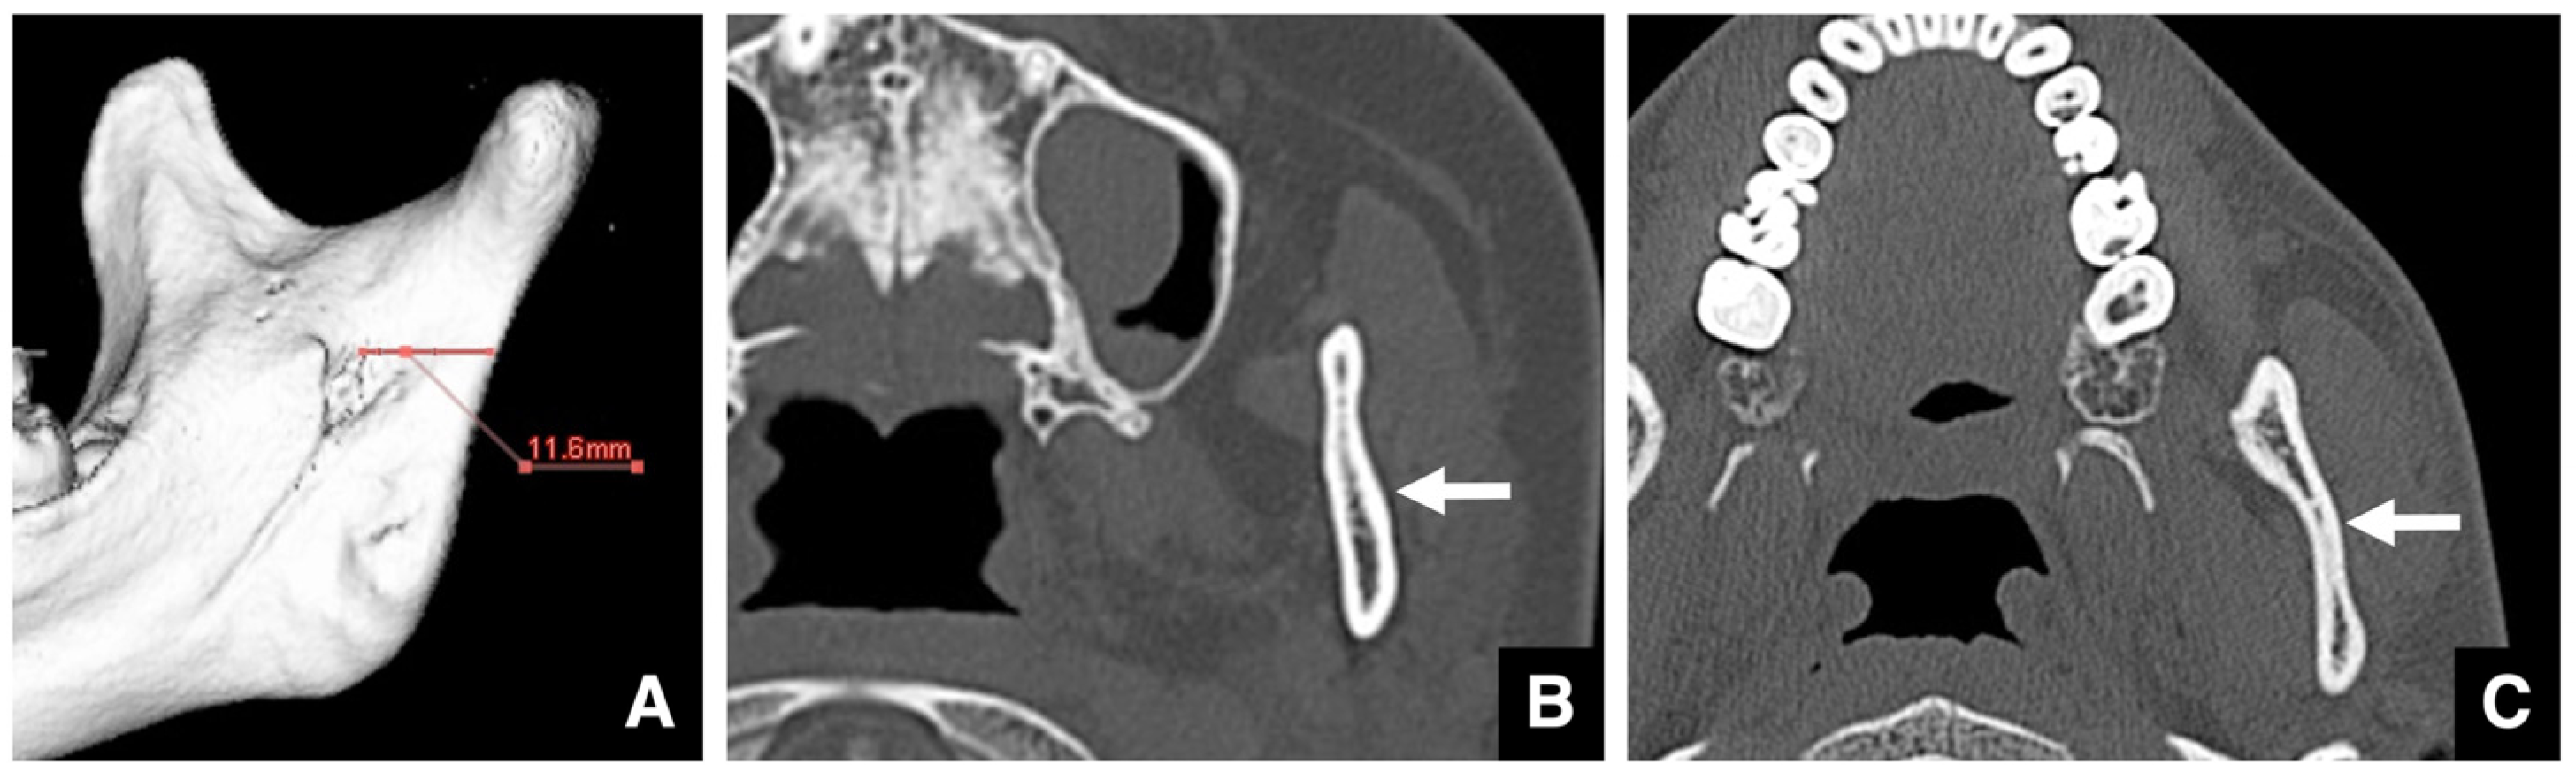

- Yoshioka, I.; Tanaka, T.; Khanal, A.; Habu, M.; Kito, S.; Kodama, M.; Oda, M.; Wakasugi-Sato, N.; Matsumoto-Takeda, S.; Fukai, Y.; et al. Relationship between inferior alveolar nerve canal positions at the mandibular second molar in patients with prognathism and the possible occurrence of neurosensory disturbance after sagittal split ramus osteotomy. J. Oral Maxillofac. Surg. 2010, 68, 3022–3027. [Google Scholar] [CrossRef]

| Setting the osteotomy line 1. Evaluation of the position of the mandibular canal and surrounding bone quality Presence or absence of mandibular canal bifurcation and course of resection site Distance from the buccal wall of the mandibular canal to the buccal cortical bone margin Bone quality around the mandibular canal (CT number) 2. Distance from the mandibular notch to the lingula Whether it is 14 mm or more 3. Morphology of the mandible and variation in cortical bone thickness Cortical bone thickness in the medial osteotomy area and lateral osteotomy area Enhanced safety through improved visibility 1. Medial curvature of the mandibular ramus Mandibular ramus is straight or strong curvature 2. Course of small blood vessels along the bone surface Depression of the buccal-lingual cortical bone from the mandibular fossa to the mandibular ramus region, trabecular bone defect Improved success rates through enhanced postoperative bone integration 1. Degree of interference between bone segments The presence or absence of interference between the proximal and distal bone segments formed during virtual mandibular deformity surgery |